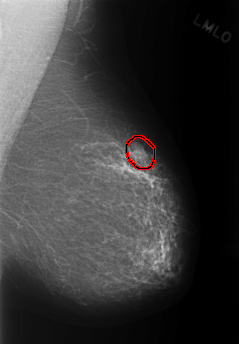

FILE: C_0331_1.LEFT_MLO.OVERLAY

TOTAL_ABNORMALITIES 1

ABNORMALITY 1

LESION_TYPE MASS SHAPE LOBULATED MARGINS OBSCURED

ASSESSMENT 3

SUBTLETY 5

PATHOLOGY BENIGN

TOTAL_OUTLINES 1

BOUNDARY